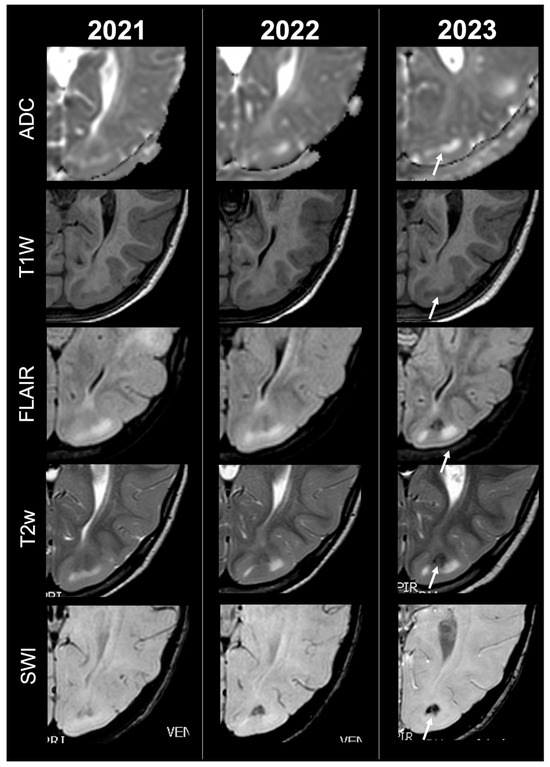

Cortical Tubers’ Transformation in Pediatric Patients Diagnosed with Tuberous Sclerosis Complex: A Retrospective Longitudinal MRI Analysis

by Camilla Russo, Simone Coluccino, Maria Fulvia De Leva, Stefania Graziano, Carmela Russo, Federica Mazio, Maria De Liso, Domenico Cicala, Anna Nastro, Federica Palladino, Serena Troisi, Pietro Spennato, Giuseppe Cinalli, Antonio Varone and Eugenio Maria Covelli

Background: Cortical tubers (CTs) are hallmark brain lesions in tuberous sclerosis complex (TSC), historically considered stable in number over time; prior literature has correlated overall CT burden on magnetic resonance imaging (MRI) with disease severity. As longitudinal imaging studies assessing CTs’ evolution over time are lacking, we aim to investigate temporal changes in CTs—both in number and signal—on MRI in a cohort of pediatric TSC patients. Methods: A retrospective single-center analysis was conducted on 57 pediatric TSC patients who underwent longitudinal MRI studies in a 10-year span. Required MRI sequences included volumetric unenhanced T1-weighted, SWI, T2w and/or FLAIR. CTs were evaluated by two neuroradiologists and classified into five subtypes (A, B, C1, C2, D) according to signal characteristics. Statistical comparison was performed using t-tests. Results: Paired t-test analysis demonstrated a significant longitudinal increase in the overall number of CTs, rising from 16.11 ± 12.43 at baseline to 18.77 ± 13.29 at follow-up (mean difference = −2.67, 95% CI [−3.94, −1.39]; t (56) = 4.19; p < 0.0001), corresponding to a moderate effect size (Cohen’s d ≈ 0.56). When stratified by age, patients <2 years—representing the incompletely myelinated subgroup—showed a more pronounced increase in CT burden, from 19.46 ± 15.21 to 24.17 ± 15.75 (mean difference = −4.71, 95% CI [−7.37, −2.04]; t (23) = 3.65; p = 0.0013; d ≈ 0.75). In contrast, patients aged ≥2 years demonstrated a smaller but still significant increase, from 13.67 ± 9.45 to 14.85 ± 9.64 (mean difference = −1.18, 95% CI [−2.08, −0.28]; t (32) = 2.68; p = 0.0115; d ≈ 0.46). Direct comparison between the two subgroups using Welch’s two-sample t-test confirmed that the mean CT count in patients <2 years was significantly higher than in those ≥2 years (mean difference = 3.53 ± 1.36; t = 2.59; df = 28.4; p = 0.0075), with a large effect size (Cohen’s d ≈ 0.78). Type C1-C2 tubers evolved from pre-existing earlier-stage lesions, while most newly visible CTs over time were type A-B. Type D tubers remained rare and derived from earlier-stage CTs. Conclusions: Contrary to previous assumptions, CTs in pediatric TSC showed a tendency to increase in number and evolve in signal over time, thus challenging the notion of stability and suggesting dynamic behavior. Incomplete myelination in early infancy may impact MRI CTs detection by reducing contrast with surrounding brain tissue, potentially leading to their underestimation/misidentification. Full article

Show Figures

Figure 1